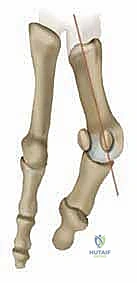

الفهم التشريحي العميق: ماذا يحدث داخل القدم عند الإصابة بالورم الأروح؟

لفهم عبقرية الجراحة التي يجريها الأستاذ الدكتور محمد هطيف، يجب أولاً أن نفهم ميكانيكية القدم. تتكون القدم البشرية من شبكة معقدة من العظام، الأربطة، والأوتار التي تعمل معاً لتوزيع وزن الجسم وتسهيل الحركة.

ورم إبهام القدم الأروح ليس مجرد "نمو عظمي زائد" كما يعتقد الكثيرون، بل هو خلل ميكانيكي وتشريحي معقد يصيب المفصل المشطي السلامي الأول (First Metatarsophalangeal Joint - MTP).

* انحراف العظمة المشطية الأولى: تبدأ العظمة المشطية الأولى (العظمة الطويلة التي تسبق الإبهام) بالانحراف نحو الداخل (باتجاه القدم الأخرى).

* انحراف السلامية (الإبهام): كرد فعل، ينحرف إصبع الإبهام نفسه نحو الخارج (باتجاه الأصابع الصغيرة للقدم).

* بروز المفصل: هذا الانحراف المتعاكس يؤدي إلى بروز رأس العظمة المشطية الأولى، مكوناً الكتلة العظمية المؤلمة التي نراها من الخارج.